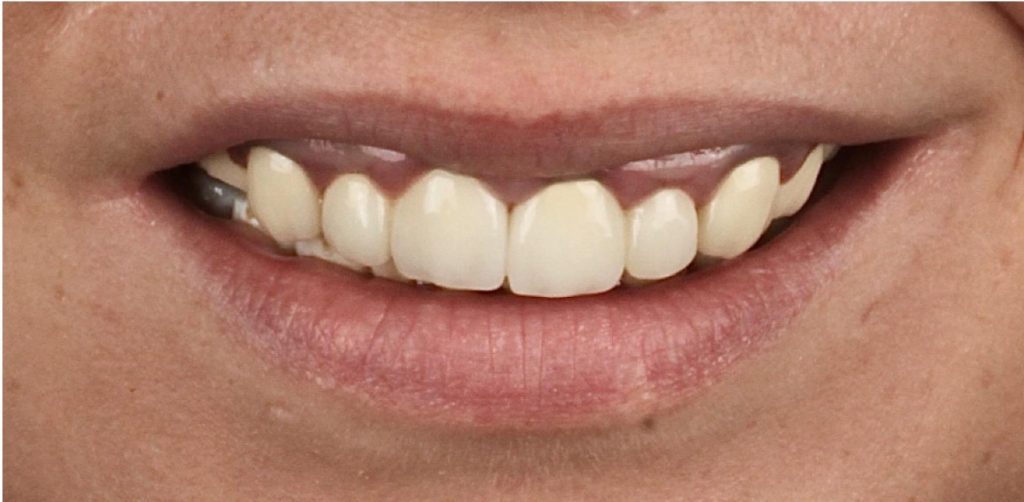

Aby osiągnąć taki efekt, musieliśmy przeprowadzić ekstrakcję złamanej górnej jedynki i w jej miejsce jednoczasowo wszczepić implant, a następnie na pozostałe zęby wykonać licówki i korony pełnoceramiczne w najjaśniejszym odcieniu.

Całość została zaprojektowana w harmonii z twarzą i rodzajem uśmiechu naszej Pacjentki. Leczenie trwało 3 miesiące.

Wykonał je lek.stom. Michał Badowski we współpracy z laboratorium Dentalscan (tech.dent. Joanna Gancarz).